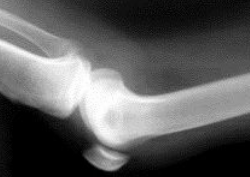

临床案例

2023年北京积水潭医院收治的老年髋部骨折患者中,早期每日饮用骨头汤组比均衡饮食组平均愈合时间延长2.3周。建议初期优先补充优质蛋白(如鱼肉、蛋清)和维生素C(促进胶原合成)。